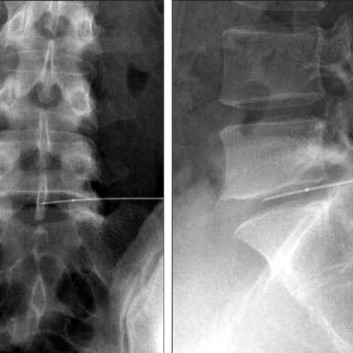

신경을 압박하는 디스크의 크기를 고주파 열응고술을 통해 감소 시키는 방법으로 급성 및 만성 디스크 병변과 척추관 협착증을 치료 합니다. 고주파 열을 이용하여 디스크의 크기를 줄일 뿐만 아니라 통증의 원인이 되는 신경을 치료하여 시술의 만족도가 높습니다.